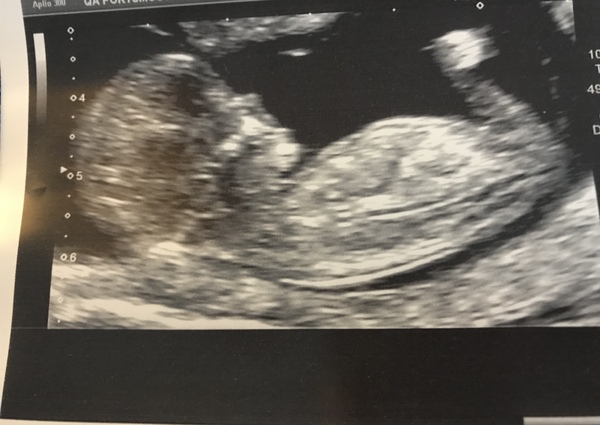

peterpanwendy · 09/03/2018 17:46

I can't work out if the little bit to the right is the other foot or the nub Grin

PetermanWendy I can’t really tell from your picture have you got any more that are centralised ? From what I see, it could be either because it’s only slightly tilted.

@Gem173 no that's the only one that you can see it in! Never mind I don't have long to wait only 11 days ❤️💙

Wendy I think boy, Gem I think girl :)

Oh no! Other way around, sorry. Gem's looks like a boy and Wendy's a girl.